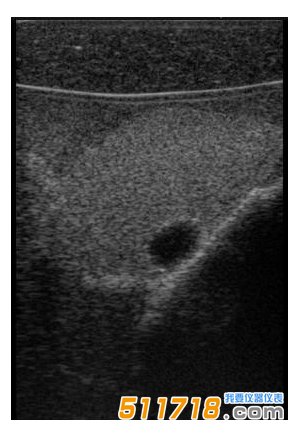

CIRS 074甲狀腺超聲訓練模體包含一個略微擴大的甲狀腺,位于一個擬人化的頸部。下巴和鎖骨被提供作為外部解剖標志。體模提供氣管,頸內(nèi)靜脈和頸總動脈作為內(nèi)部解剖標志。每個甲狀腺葉包含一個囊腫和一個等回聲僵硬病變。可以在甲狀腺內(nèi)定制生產(chǎn)各種結(jié)節(jié)。*有材料都配制成超現(xiàn)實的。

略微擴大的甲狀腺包含單個囊腫和每個葉中的一個等回聲,僵硬的病變。

可以對每個囊腫進行細針抽吸。每個僵硬病變都設(shè)計用于超聲彈性成像的可視化,并且可以進行活組織檢查。這些病變對甲狀腺是等回聲的并且具有標準的B模式成像。

單純囊腫